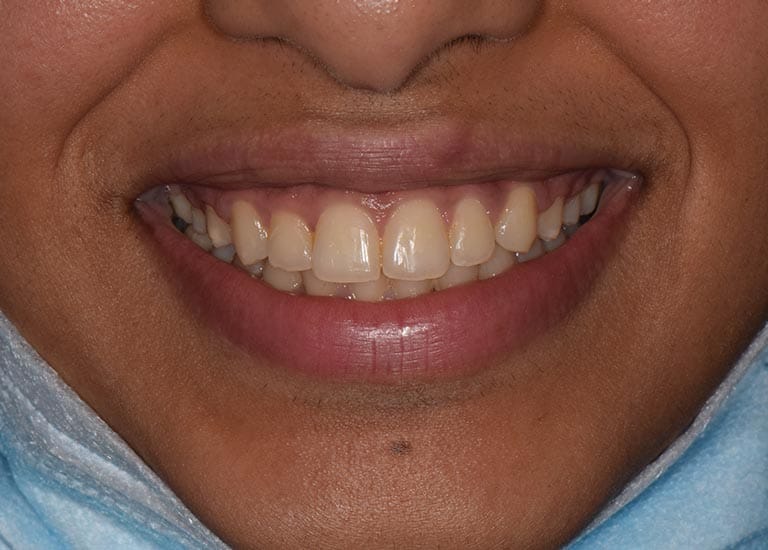

AFTER

The teeth overlay was treated orthodontically by means of fixed braces and without any tooth extraction. We also pulled the posterior molars forward to close the gap successfully, and the gummy smile was almost solved without the need for surgery.